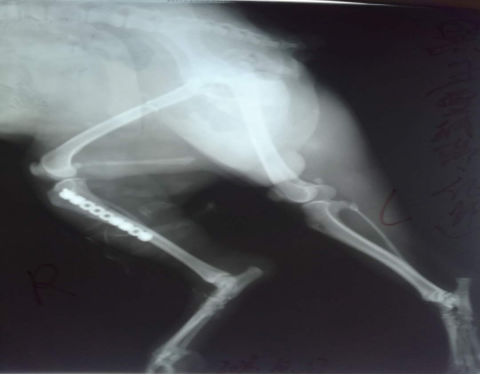

雪納瑞大黑被車撞到,導致右后腿無法站立,X光檢查脛骨骨折,在別的醫(yī)院拍完X光后轉到我院進行手術,經過精心手術成功斷端成功對接,剩下的只需要主人的精心呵護***痊愈。也提醒廣大寵物主人一定要看好自己的寵物,不要亂跑以防出現事故。